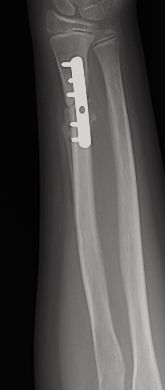

Figura 11: a, b-Fractura metafiso-diafisaria distal inestable. c, d-Control radiológico tras reducción donde se aprecia mala reducción. e, f-Síntesis mediante placa y tornillos.